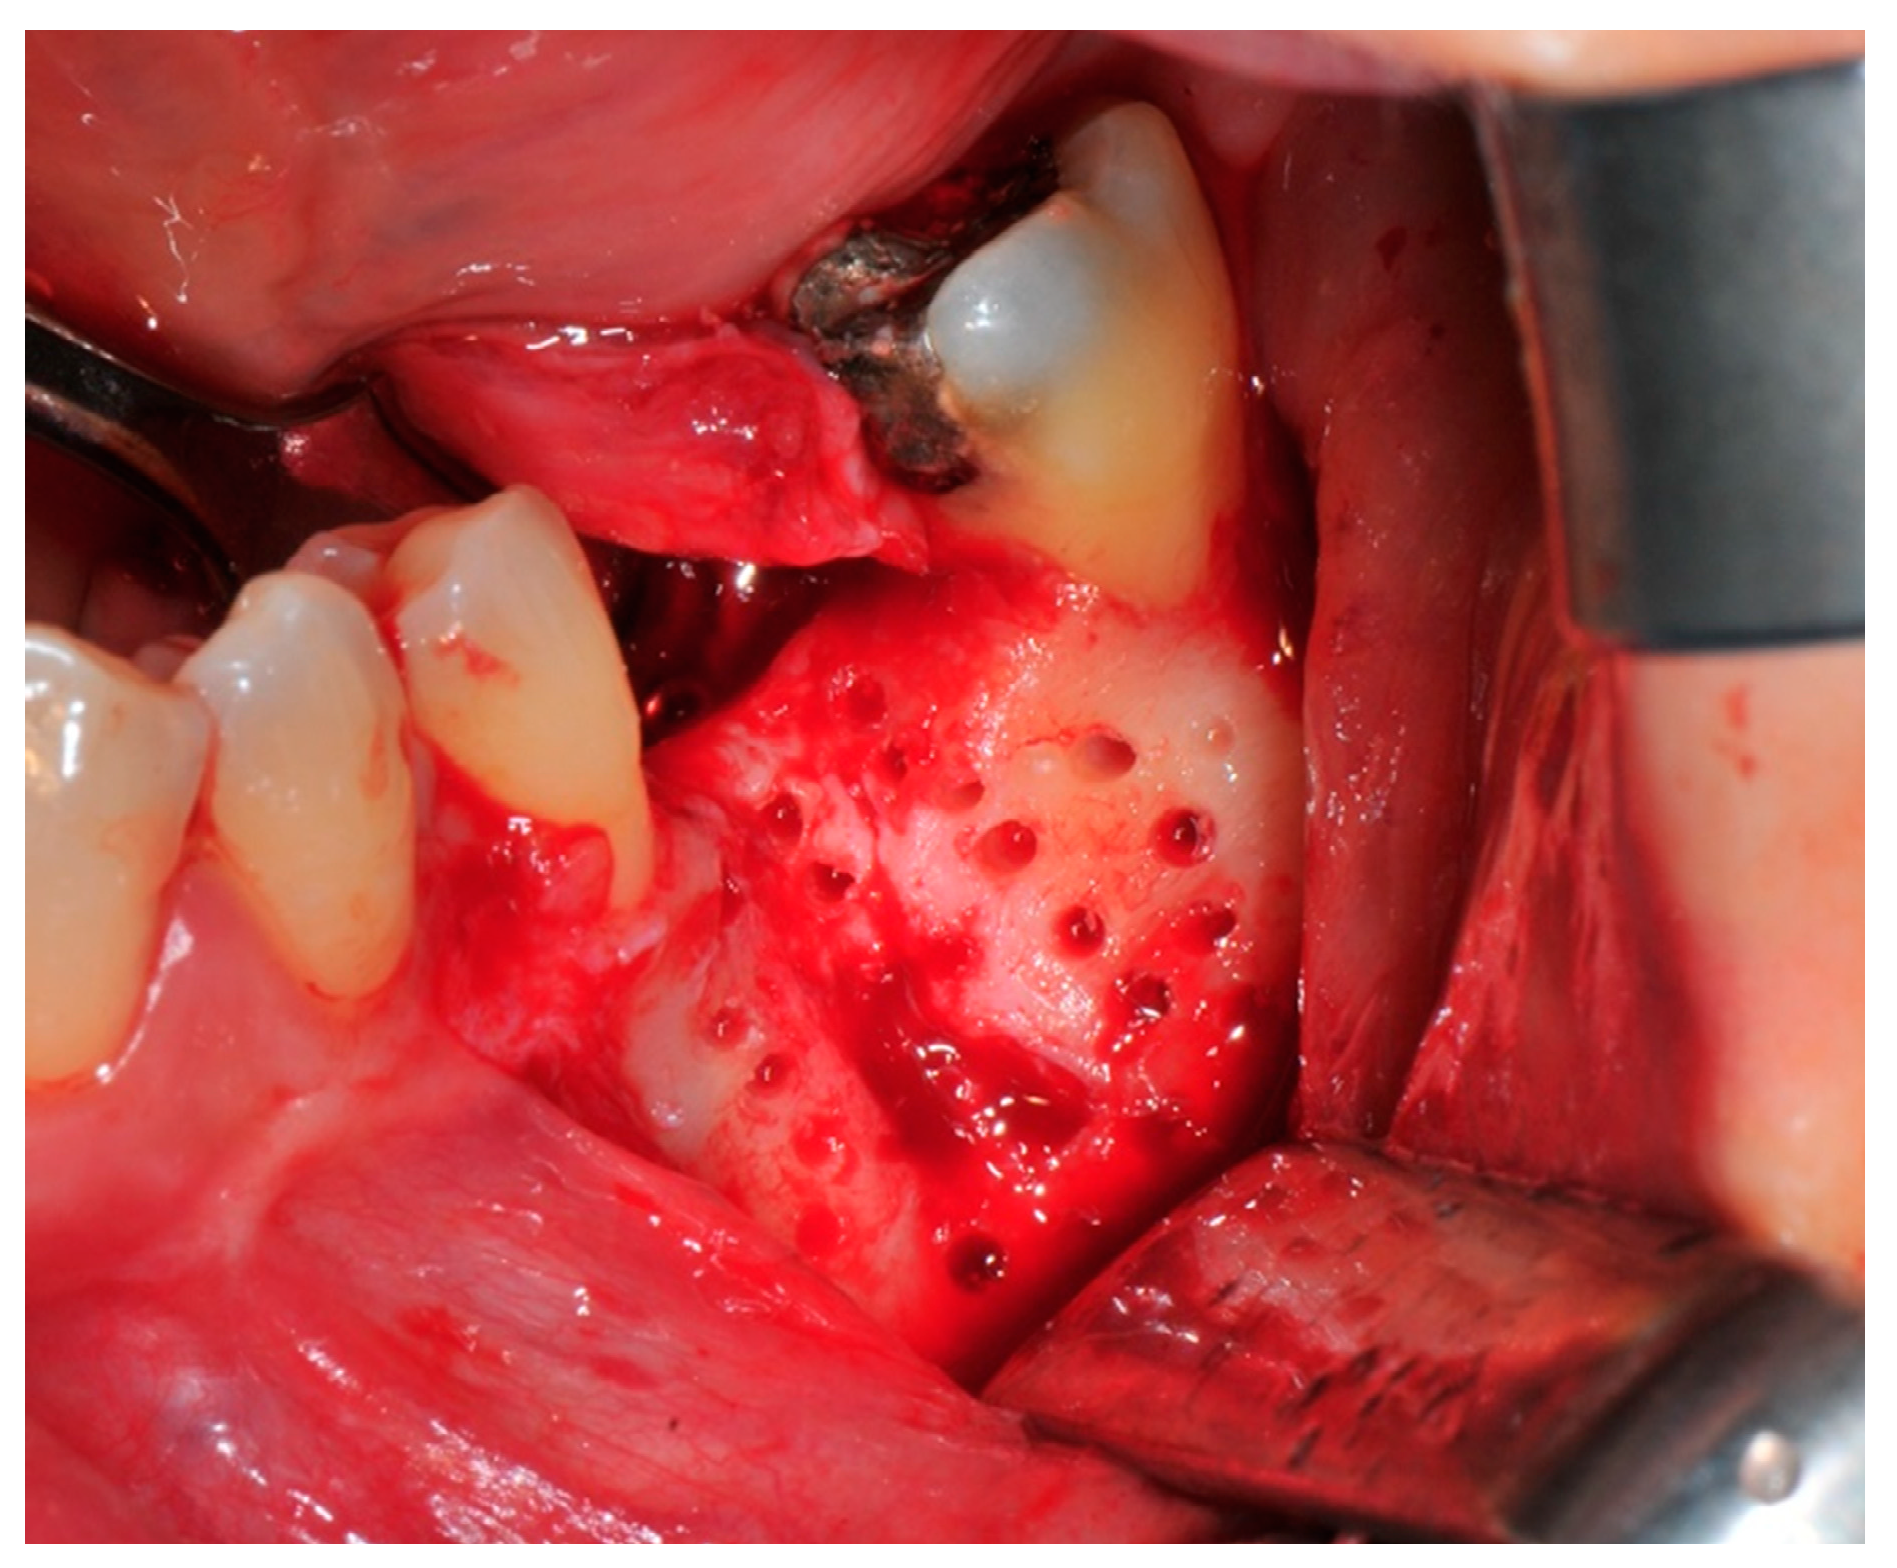

- Preparation of the receiving site: The exposed bone is cleaned from all of the remaining soft tissue and it is then prepared with multiple perforations using a small ball bur; this procedure is known as “bone refreshing” and it is performed to expose the cancellous portion of the residual bone, which shows a great osteo-genetic potential (Figure 6).